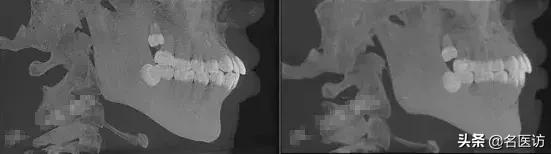

医生很亲切,小姐姐们也很可爱。了解到我的情况以后,医生给我的牙齿拍了片子,确定了拔牙矫正的方案。

而且医生跟我讲,每个人的面型不同,不是内收的越多越好,还要根据面型来判断内收的量。

如果是骨性嘴突,一般就要需要做手术了。

嘴突,完全是因为骨头原因造成的,就算是做矫正也没有效果,所以一般这种情况下医生会建议你做手术。

骨性嘴突